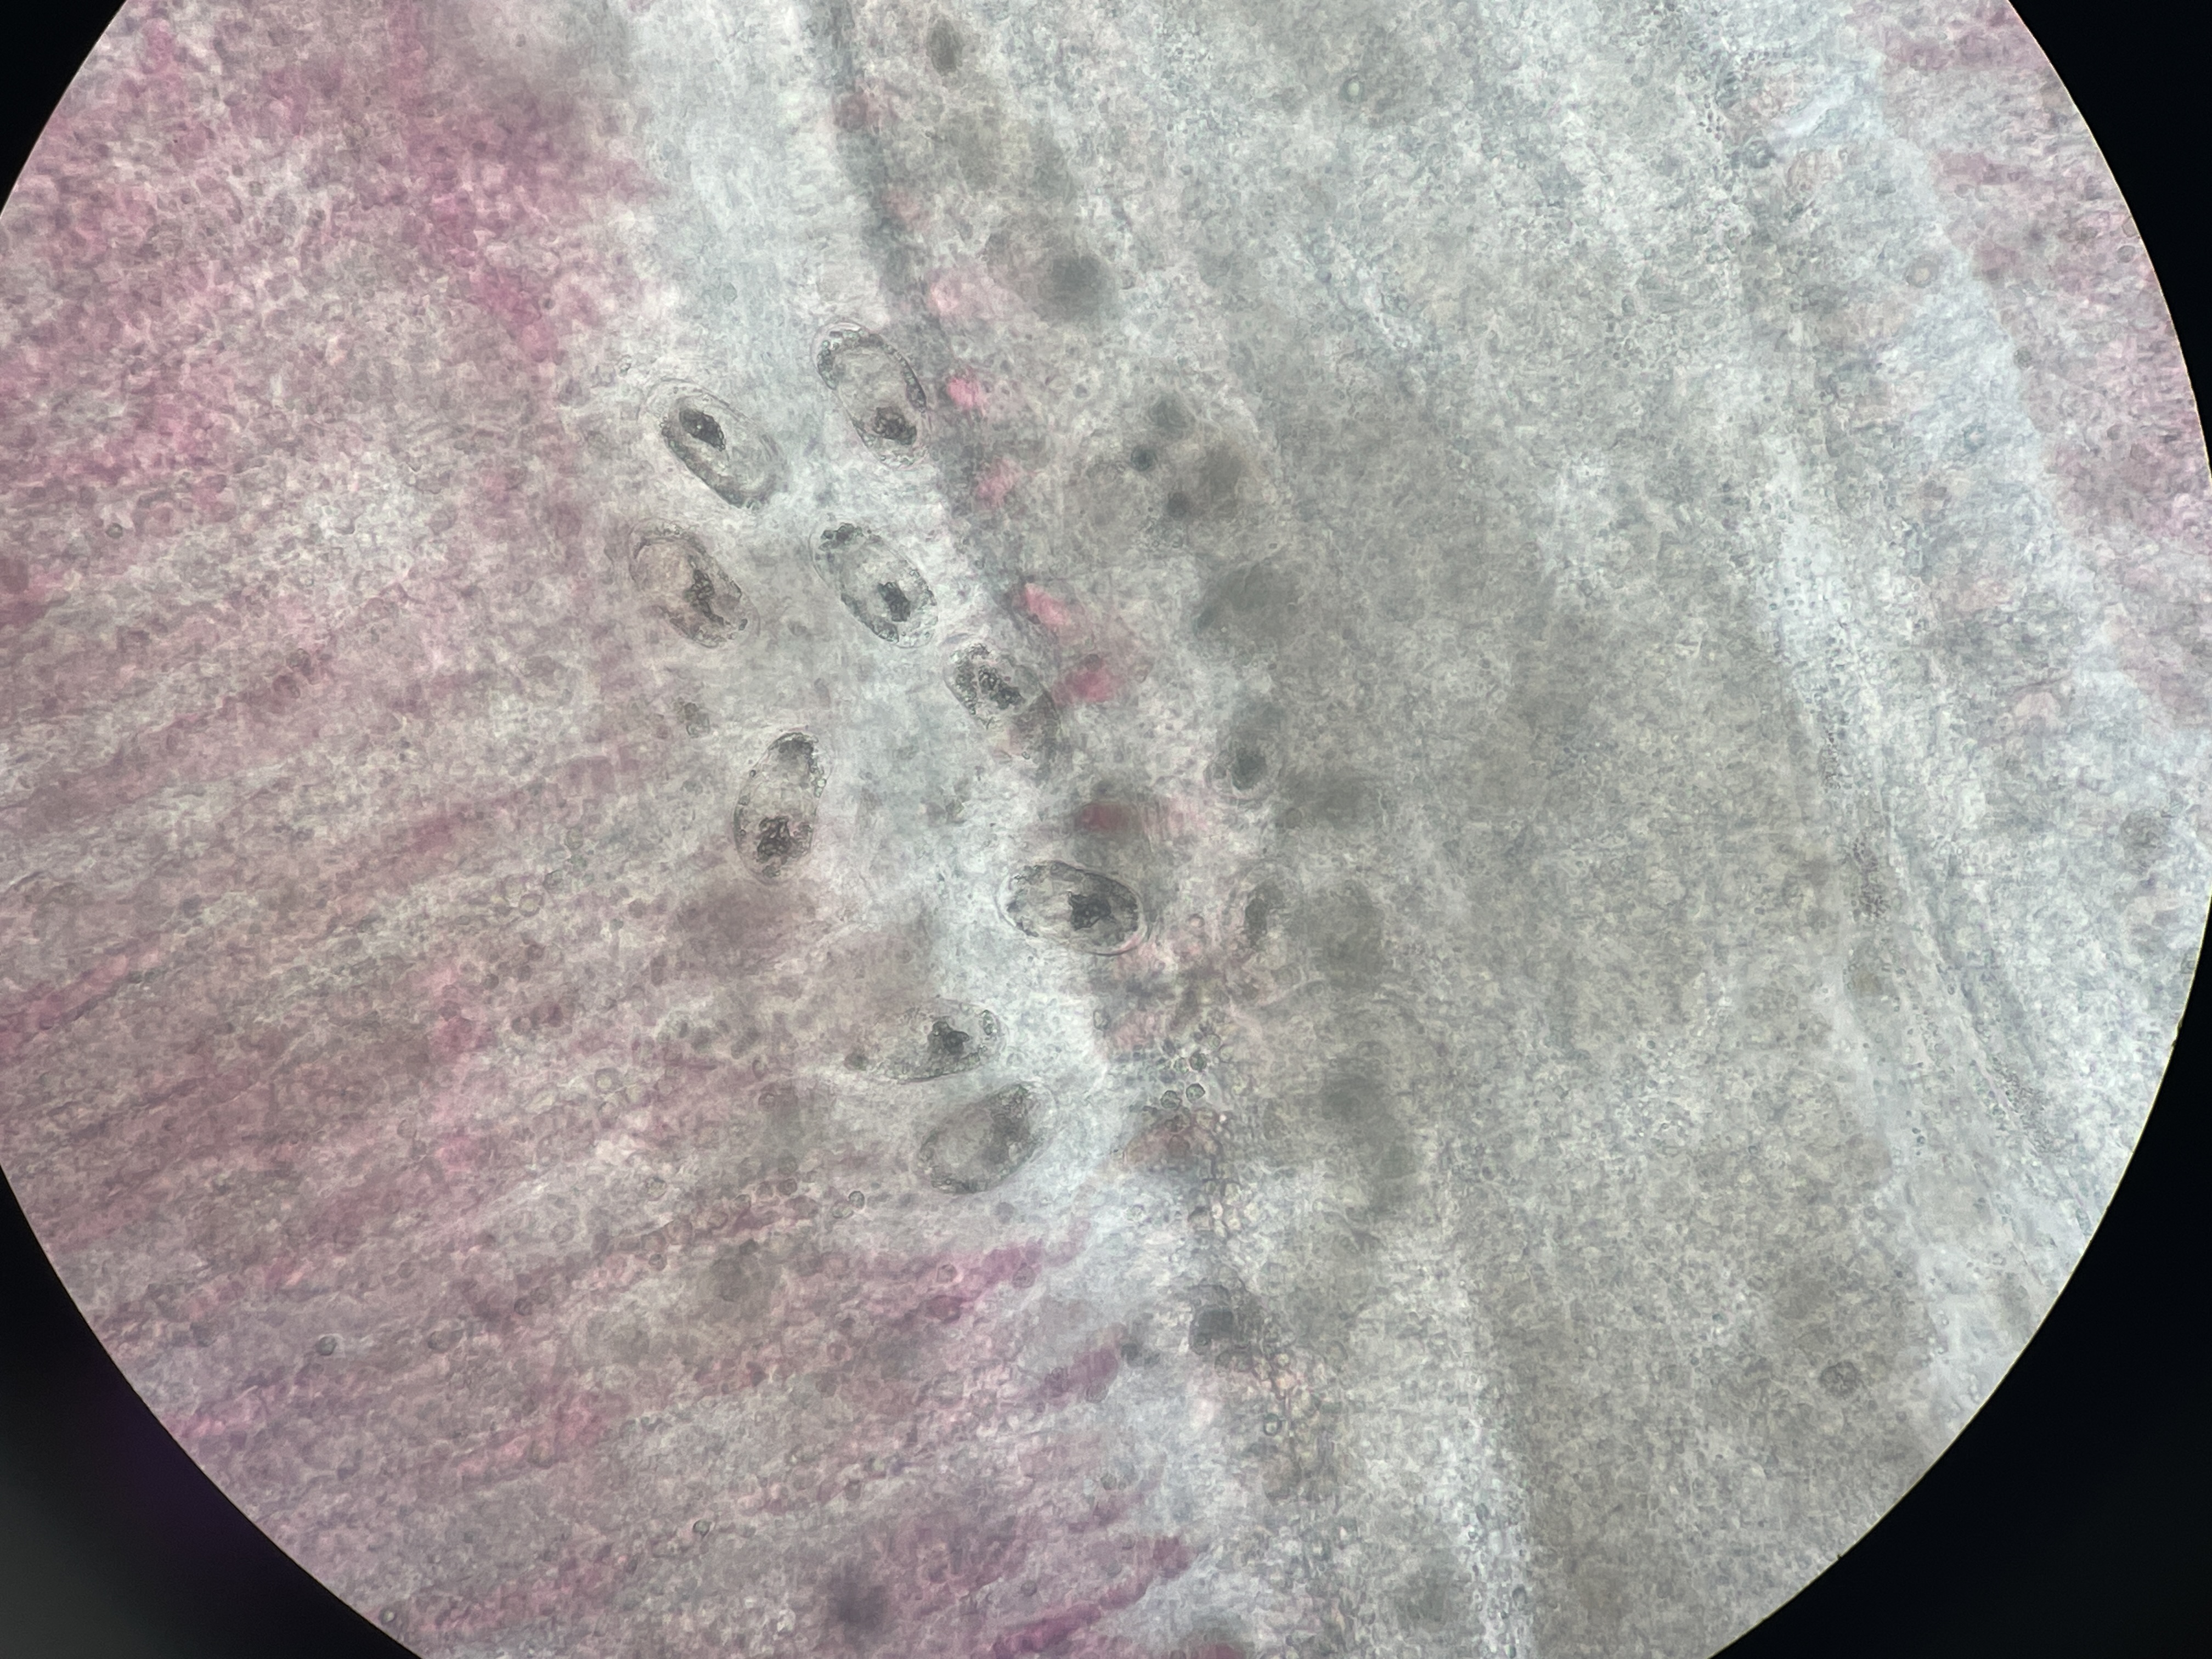

Trematode Digenean Parasitosis

Agent: Cardicola aurata (Sanguinicolidae, Digenean parasite).

Symptoms: Adult parasites reside in the heart and major blood vessels of the gilthead sea bream. Their eggs travel through the bloodstream to reach the gill capillaries causing capillary rupture and allowing the larvae to exit into the environment and resulting in what is known as “white gill syndrome.” Diagnosis is made by observing eggs in gill capillaries in fresh preparations.

Control: No treatment.